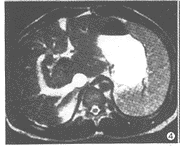

19例中,肝脏增大18例(95%),尾叶增大14例(74%)。14例(74%)肝脏信号不均,T2WI呈斑片状稍高信号,T1WI呈稍低信号且较明显(图1~3)。7例(37%)显示下腔静脉入右心房处阻塞;4例(21%)下腔静脉内有血栓影,表现为T1WI呈等信号,T2WI呈稍高信号;下腔静脉肝后段裂隙样狭窄10例(53%)。19例(100%)均显示肝静脉狭窄或阻塞,其中累及左肝静脉15例,中肝静脉13例,右肝静脉11例。17例(89%)见有肝内侧支血管呈“逗号”样或迂曲、走行无规律的血管影,5例(26%)显示有副肝静脉,呈粗大的血管影自肝右叶连于下腔静脉的右侧壁(图4~6)。17例(89%)见有肝外侧支血管,其中7例腹壁静脉曲张,14例(74%)有粗大的奇静脉和/或半奇静脉影,膈下静脉曲张3例,胃底静脉曲张3例。脾脏增大16例(84%),7例(37%)有腹水。

图3 T1WI显示肝尾叶明显增大,半奇静脉、椎旁静脉扩张

超声、CT、静脉造影是BCS的常用检查方法,其中静脉造影是诊断以及介入治疗本病的主要依据。静脉造影可以明确狭窄或阻塞的部位和类型,了解侧支血管。MRI检查有无创性、多平面、多参数等优点[1~4],对于显示肝脏大小、形态以及邻近的实质性脏器优于超声和静脉造影。BCS常表现为肝脏增大,本组有18例显示肝脏增大。尾叶由于有单独的静脉回流到下腔静脉,增大较明显,本组有14例。区域性肝脏充血、中央小叶坏死及含水量的增加使得肝脏信号不均匀[3],T1WI呈低信号,T2WI呈高信号。T1WI、T2WI均呈低信号则提示肝纤维化。本组中14例有肝信号不均的表现,T1WI显示例数较T2WI稍多。

作为一种非侵袭性的检查手段,MRI对于血管的显示有独特的价值[1,5],BCS表现的下腔静脉和肝静脉异常能得到较好的显示;MRA可以更为直接显示血管情况,有利于了解大血管的情况以及与右房的解剖关系,对于选择治疗方法和制定介入或手术方案有较大的帮助。肝后段下腔静脉狭窄呈裂隙样,而下腔静脉阻塞可为膜型或节段型,在冠状位或矢状位显示最佳,表现为下腔静脉内弧形软组织膜或一段下腔静脉腔闭塞[3],本组有7例表现为下腔静脉肝后段入右心房处节段性闭塞。肝静脉的异常表现有肝静脉主干狭窄和狭窄后扩张,肝静脉主干纤细或肝静脉主干影消失,本组MRI显示下腔静脉和肝静脉的异常与超声、静脉造影比较结果相似。当下腔静脉内有血栓形成时,表现为下腔静脉流空消失,腔内异常信号,优于静脉造影对于血栓的显示,本组有4例显示下腔静脉内血栓,T1WI呈等信号,T2WI呈稍高信号。